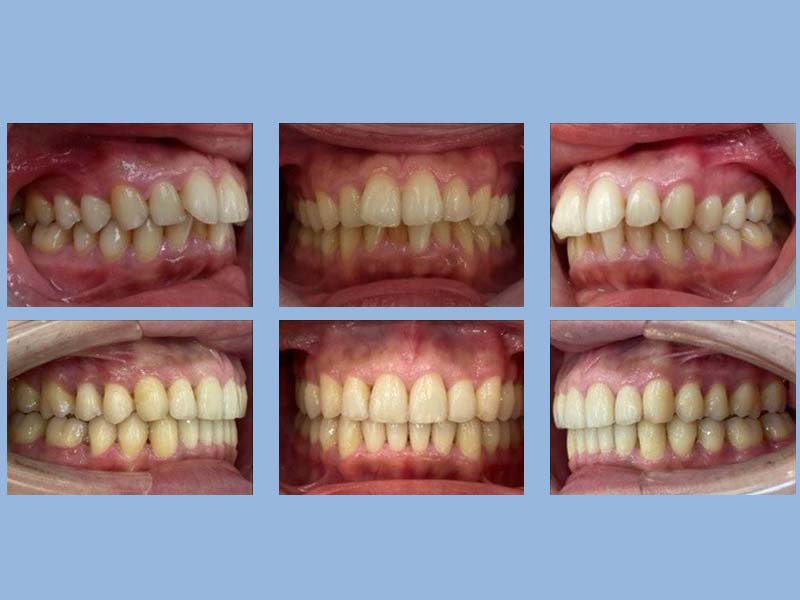

涂小姐 (25歲) 矯正完成

狀態 : 暴牙、擠、沒拔牙